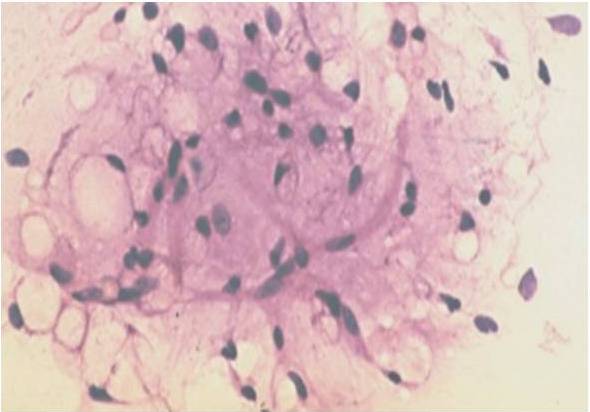

Malignant lesions in which cytological features did not permit definite subtyping were grouped under broader categories as ‘Spindle cell sarcomas ‘(Fig 1), Small round cell sarcomas (Fig 2), Epithelioid / polygonal cell sarcomas, Pleomorphic cell sarcomas (Fig 3) and Myxoid sarcomas (Fig 4).

Figure 3-Pleomorphic Sarcoma (H&E, 40 X)

Figure 4-Myxoid Sarcoma (H & E, 40 X)

In our study, cytological smears from` round cell sarcomas ‘were highly cellular and were composed of discohesive tumor cells and occasional small cellular clusters, whereas, hypercellularity was a dominant feature in `spindle cell sarcoma’ group .The tumor cells tended to be discohesive and individually dispersed  with a few scattered variably sized tumor cell  clusters. In contrast to round cell sarcomas, cytological atypia was observed more often in spindle cell sarcomas. Pleomorphism was marked in the Pleomorphic cell sarcomas whereas myxoid sarcomas showed focal myxoid areas amidst tumor cells.